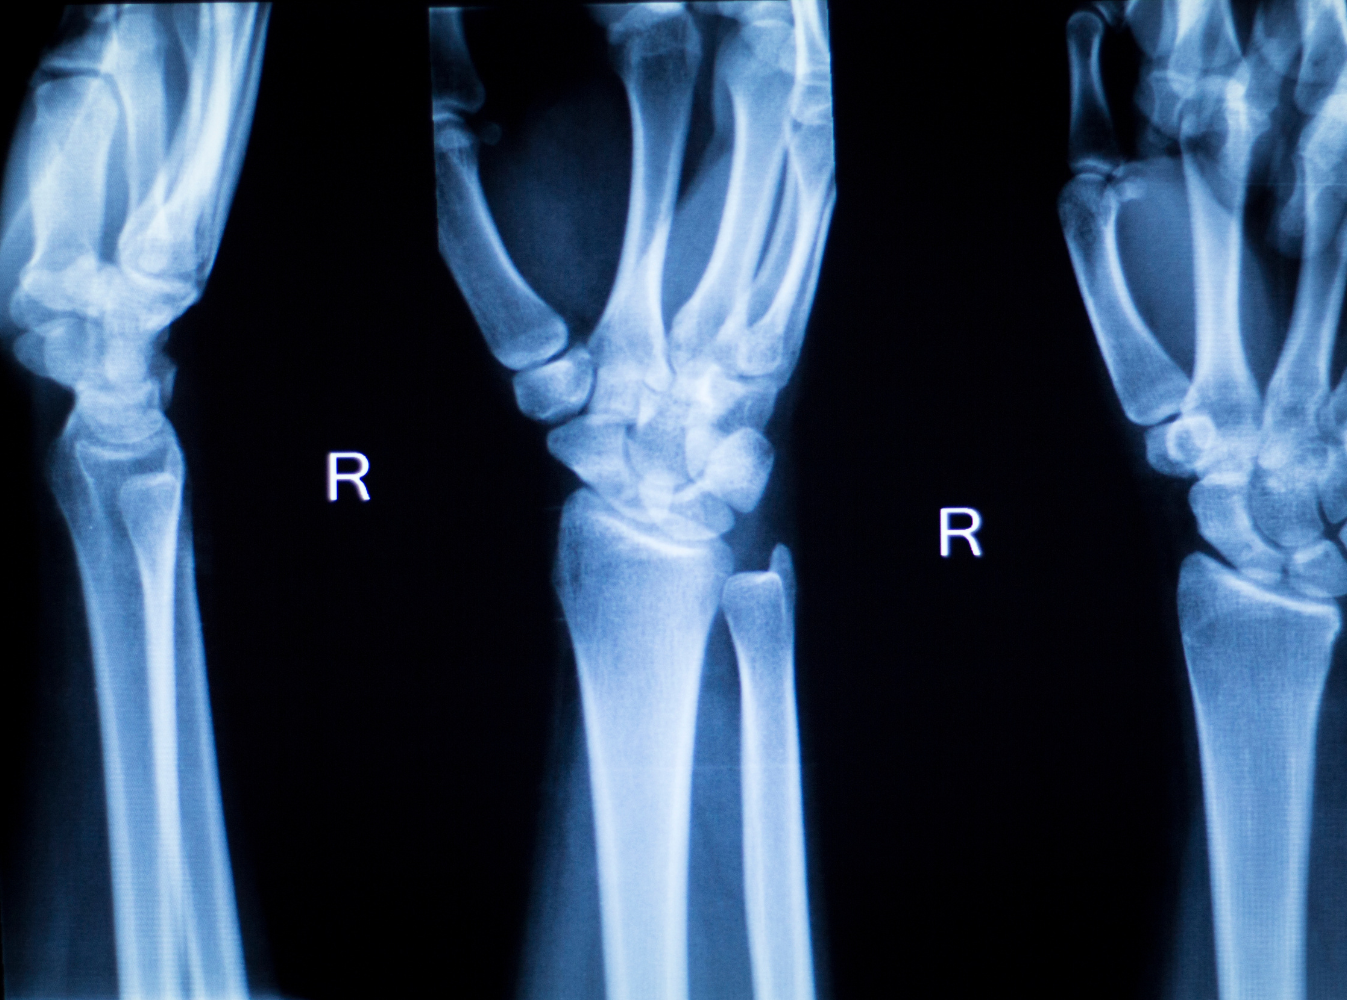

- Fractures: One of the most common injuries in a wreck, a broken wrist can take months to heal. Another common fracture, the scaphoid fracture, involves breaking another small bone in the wrist.